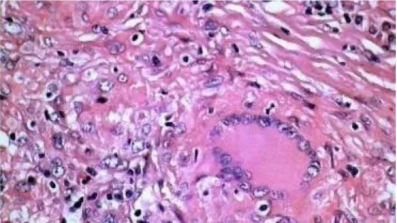

Gomori氨银染色法

1.Gomori氨银染色法

用途及原理:网状纤维呈黑色,胶原纤维呈红色。鉴别诊断中的应用:①癌和肉瘤的鉴别;②恶性淋巴瘤和组织细胞肉瘤;③血管内皮细胞瘤和外皮细胞瘤;④黏液纤维瘤和黏液肉瘤。